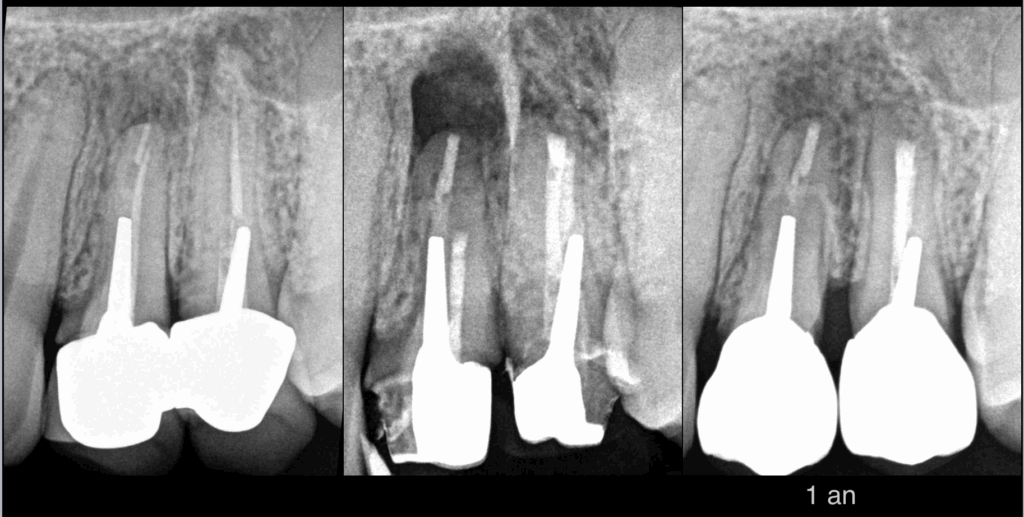

🦷 Dents 23 24

🔄 Pulpes précédemment traitées

⚠️ Parodontites apicales symptomatiques

💡 𝐑𝐞́𝐟𝐞𝐜𝐭𝐢𝐨𝐧 𝐩𝐫𝐨𝐭𝐡𝐞́𝐭𝐢𝐪𝐮𝐞 indiquée → retraitement canalaire.

🛠️ Dépose réalisée par notre cher correspondant.

➡️ Nous nous rendons compte :

• que 𝐥𝐚 𝐝𝐞́𝐩𝐨𝐬𝐞 𝐝𝐞𝐬 𝐢𝐧𝐥𝐚𝐲-𝐜𝐨𝐫𝐞 𝐜𝐨𝐦𝐩𝐫𝐨𝐦𝐞𝐭𝐭𝐫𝐚 les pronostics biomécanique et prothétique

• que 𝐥𝐞𝐬 𝐢𝐧𝐥𝐚𝐲-𝐜𝐨𝐫𝐞 𝐞𝐧 𝐥’𝐞́𝐭𝐚𝐭 sont exploitables pour la réalisation de nouvelles prothèses

✅ 𝐈𝐧𝐥𝐚𝐲-𝐜𝐨𝐫𝐞 sont laissés en place.

🤝 𝐃𝐞́𝐜𝐢𝐬𝐢𝐨𝐧 𝐭𝐡𝐞́𝐫𝐚𝐩𝐞𝐮𝐭𝐢𝐪𝐮𝐞 modifiée en accord avec le patient :

🔬 𝐌𝐢𝐜𝐫𝐨𝐜𝐡𝐢𝐫𝐮𝐫𝐠𝐢𝐞 𝐞𝐧𝐝𝐨𝐝𝐨𝐧𝐭𝐢𝐪𝐮𝐞 des canaux V et P de 24 25.